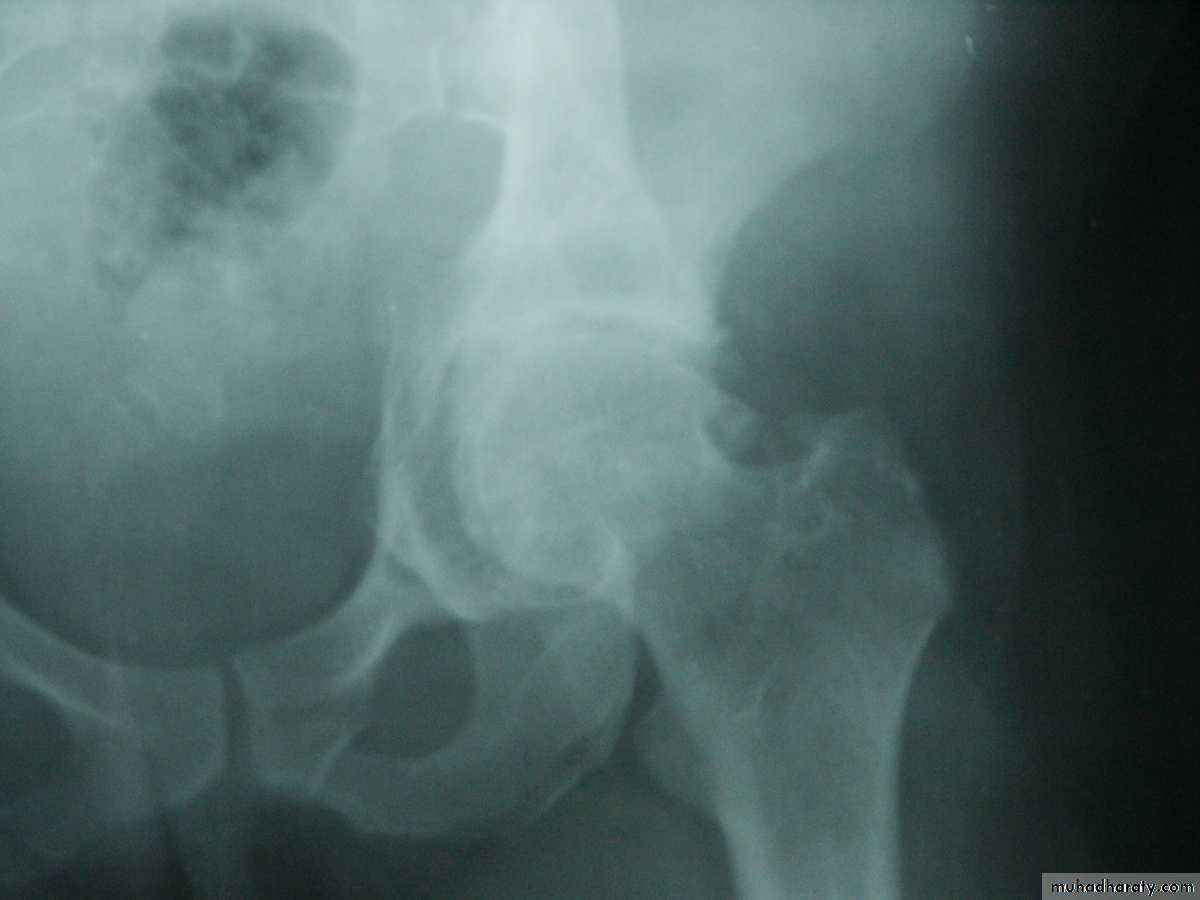

Posterior dislocation:

Mechanism of injure:4 out of 5 traumatic hip dislocations are posterior.

Usually occur in road traffic accident when the knee striking the dashboard

the femoral head is forced out of its socket sometimes associated with fracture.

and with femoral fracture to include both the hip and knee.Radiological examinations

X-R AP view we can see the dislocation with or without associated fracture posterior wall of the acetabulum,or fracture head of the femur,

And neck of femur.